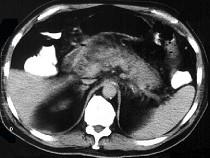

问题 男,32岁,上腹部持续性疼痛,放射至胸背部,高热,恶心呕吐,上腹部压痛反跳痛,CT检查如图,最佳的诊断是 ( )

选项 A.急性单纯性胰腺炎 B.出血坏死性胰腺炎 C.慢性胰腺炎 D.慢性胰腺炎急性发作 E.胰腺癌

答案 B